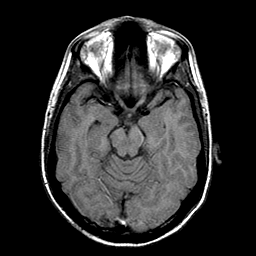

Sarcoma, MR Study #1 mr-t1 -- Slice #8

[Home][Help][Clinical] Slice 8